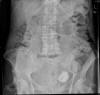

Diverticulosis de colon.

Diverticulosis de colon. Megacolon.

Dolico-megacolon.